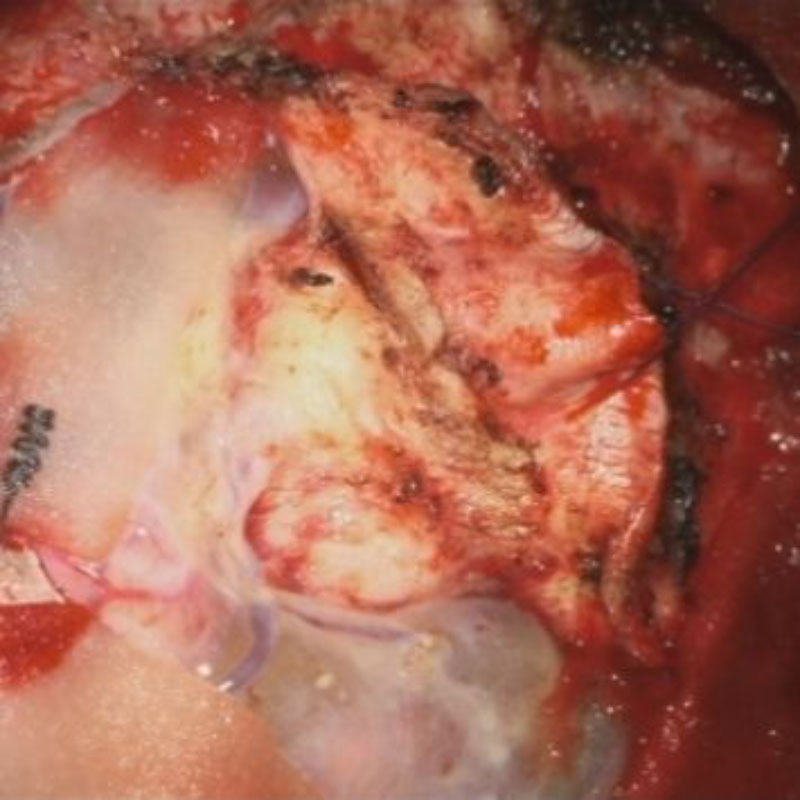

術中写真

摘出 中